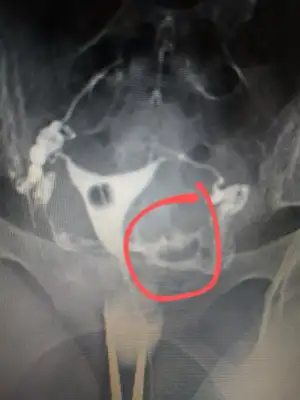

Onun hatlar karışık biraz. Çekim sonrası radyologun mesai saati bittiği için rapor yetişmemiş. Pazartesi alacak sonucunu. Kendi doktoru tüplerden birinde tıkanıklık var gibi konuşmuş ama başka doktorlara da göstermiş, basınçla açılmış demişler

pazartesi herşey sonuçlancak demek. Açılmıştır kuzum bak sorunun nerde olduğu anlaşıldı en azından en kısa zamanda gelecek beben